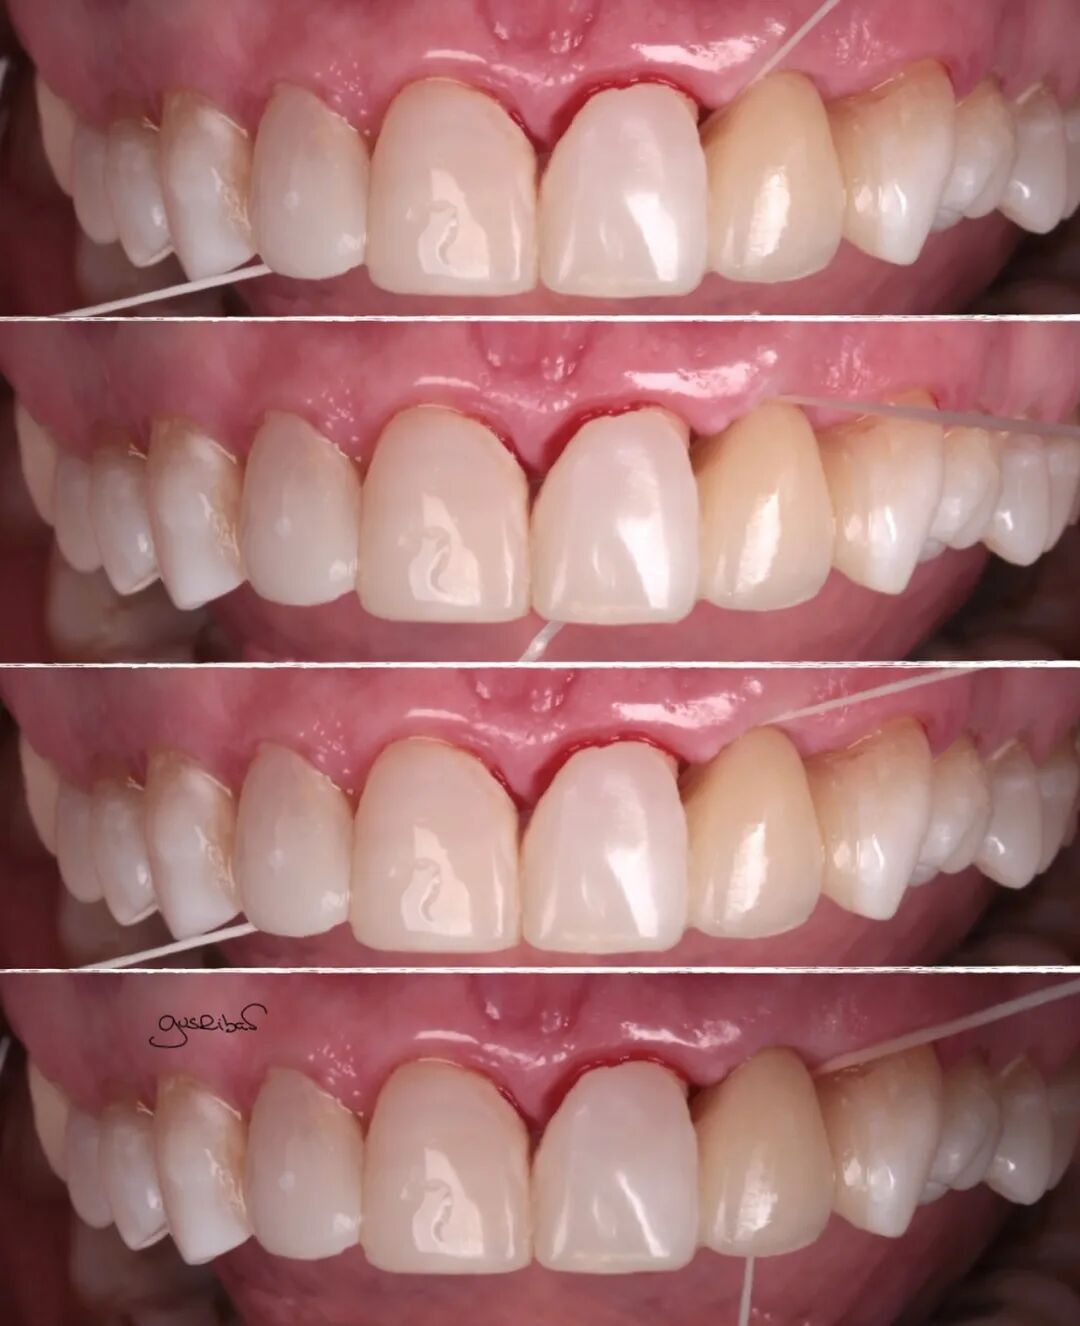

在邻牙上做了部分预备,立即封闭了暴露的牙本质,进行了数字化扫描,完成修复体的制作和美学调整,并用复合树脂进行了粘接。